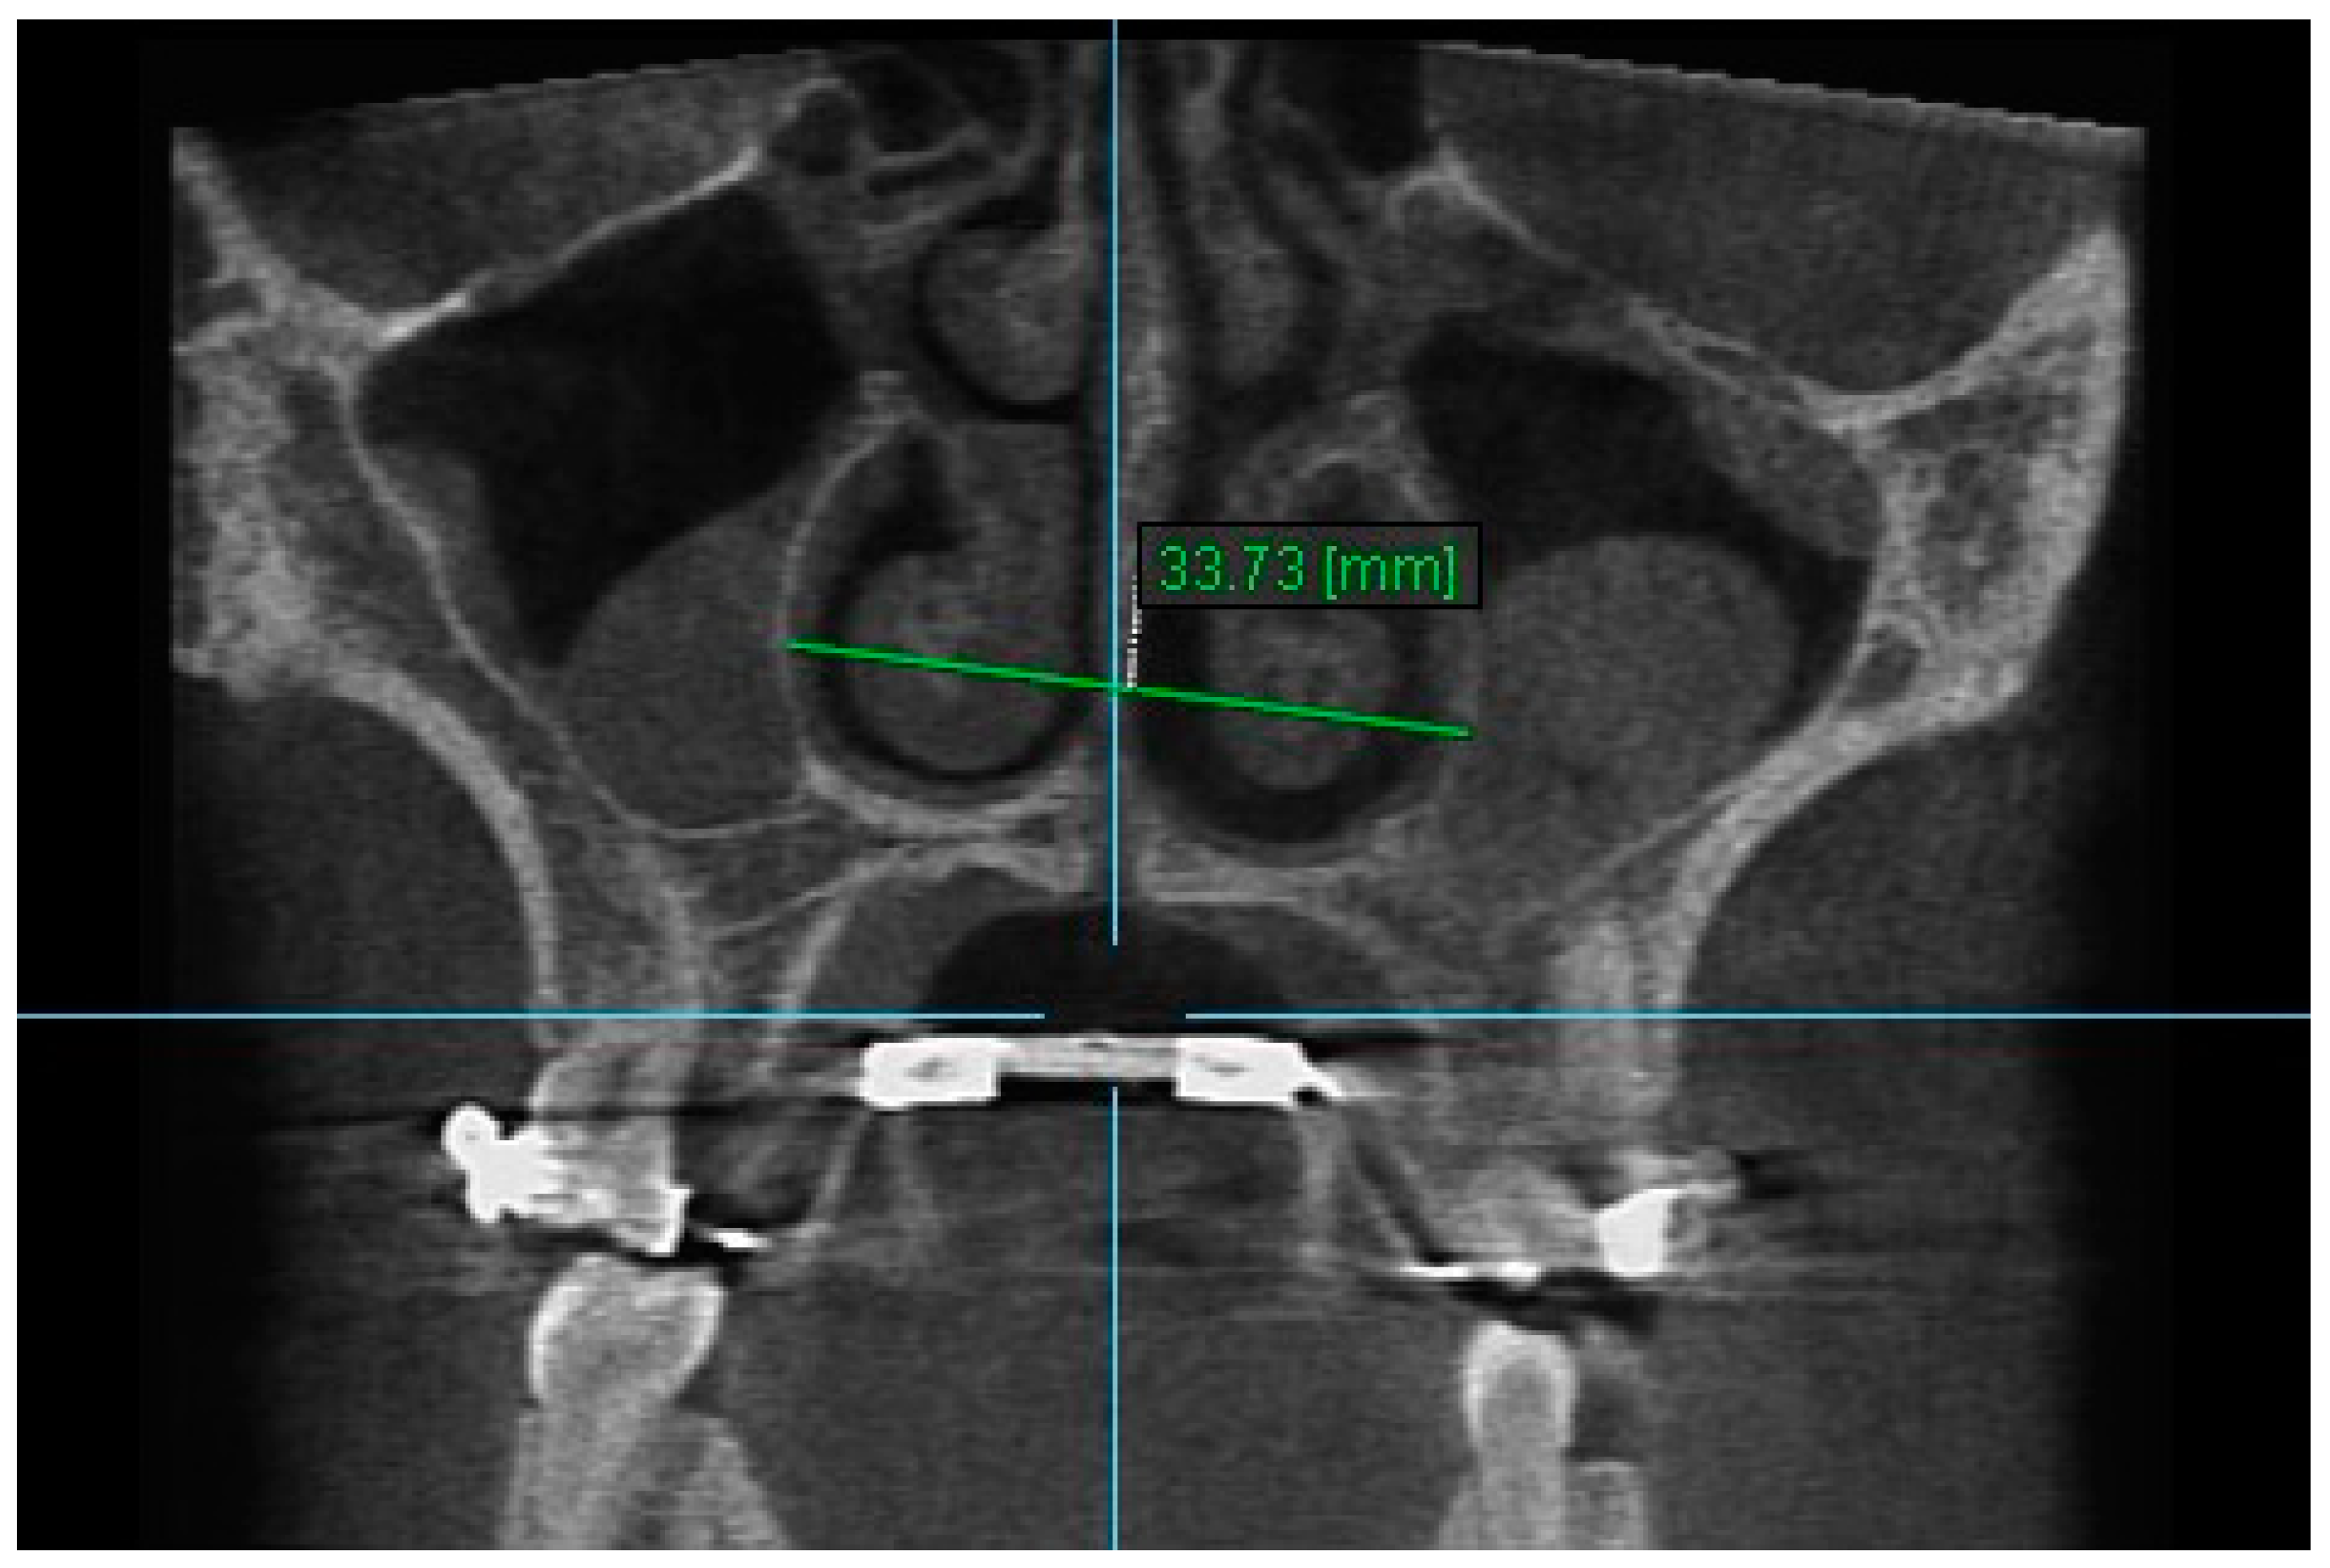

10. Aperture of Midpalatal Suture 10: The distance between the inner points of posterior median palatine suture, bilaterally in posterior nasal spine (PNS) (Figure 12).

Figure 12.

Aperture of Midpalatal Suture 10.

Statistically significant differences were found between the mean value of Apertures of Midpalatal Sutures 10 and 11 between all the time intervals, i.e., between T2–T1, T3–T1 and T3–T2 (p < 0.005). An increase in the mean values of Apertures of Midpalatal Sutures 10 and 11 were observed immediately after the end of RPE (T2–T1). Statistically significant decreases were found 6 months after RPE (T3–T2). The overall (T3–T1) differences between pre-expansion and 6 months after expansion for Apertures of Midpalatal Sutures 10 and 11 were found statistically significantly increased (Table 11 and Table 12).

Table 11.

Results of the mean differences (mm) of Aperture of Midpalatal Suture 10 in the three time intervals.

The results of this study show that the expansion of the maxilla, shown at the aperture of the midpalatal suture, has a triangular pattern. It was found that the amount of increase was greater (a) at the anterior median palatine suture, (b) bilaterally in the inferior alveolar ridge of the central incisors than the posterior, and (c) bilaterally in at posterior nasal spine (PNS). Similar results to our study have shown that the midpalatal suture has a triangle shape, with the triangle’s vertex in the PNS and its base in perspective [1,2,36,37]. According to Da Silva et al. [38], the palatal suture has its largest width in the anterior region and does not have a parallel opening configuration in the axial plane. Additionally, Kartalian et al. [39] found that after RPE, the midpalatal suture separates in a nonparallel manner in response to expansion forces. The maxilla articulates with unpaired bones, which limits the amount of separation. Caldas et al. [40], studying the effect of rapid maxillary expansion on the nasal cavity assessed with cone-beam computed tomography, concluded that there is a great transverse movement and subsequent separation of the nasal conchae from the nasal septum in both the anterior and posterior sections of the inferior portion of the lateral walls of the nasal cavity after RPE.